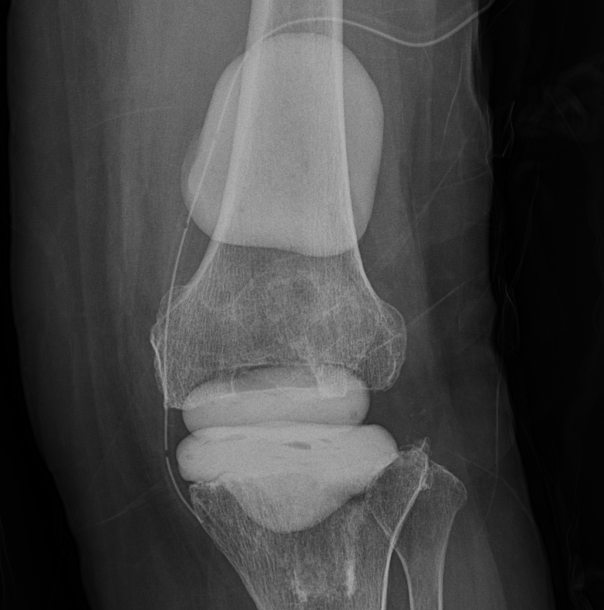

TKRA vs PROSTALAC(Prosthesis of Antibiotic-Loaded Acrylic Cement) X-ray

Prostalac은 감염된 인공관절을 제거한 뒤 감염을 치료하면서 환자가 일정 부분 관절을 사용할 수 있도록 항생제 방출하며 감염 치료를 돕는 항생제 함유 관절스페이서를 뜻함. 적응증1)인공관절 감염2)통상적으로 2단계 인공관절 재치환술 시행 시 사용 장점1)관절 운동 유지, 근위축과 구축 방지2)국소 항생제 농도 높여 감염 치료3)최종 인공관절 재치환 시 유리한 환경 제공 단점1)장기적 사용 불가 - 내구성이 떨어짐2)감염 치료가 안되면 추가 수술 필요